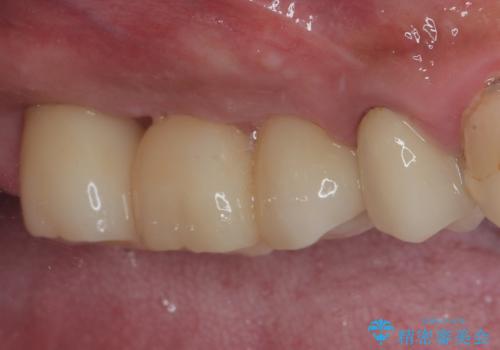

術後にインプラントの安定値を測定し、十分な値が達成された後、速やかにセラミッククラウンにて補綴治療を行うこととしました。

強い咬合力により歯根破折を繰り返しているため、即日荷重あるいは早期荷重による他の歯への負担を軽減することが重要となります。

抜歯即時埋入インプラントは、咬合力によるトラブルを回避する、非常に有用な手段となります。